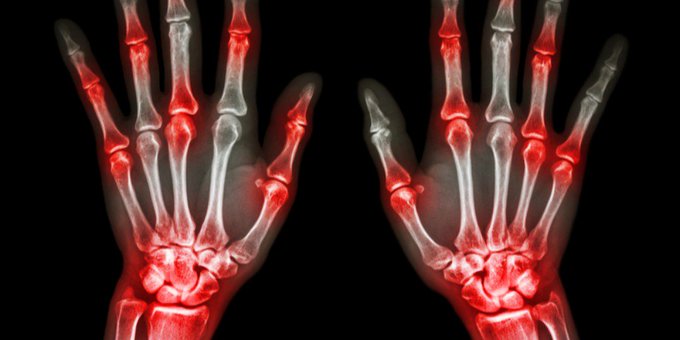

¿Sabías que existen más de 100 tipos de artritis? La mayoría de los tipos de artritis causan dolor e hinchazón en las articulaciones. Aquí lo que debes saber ow.ly/gauj50xfPzs